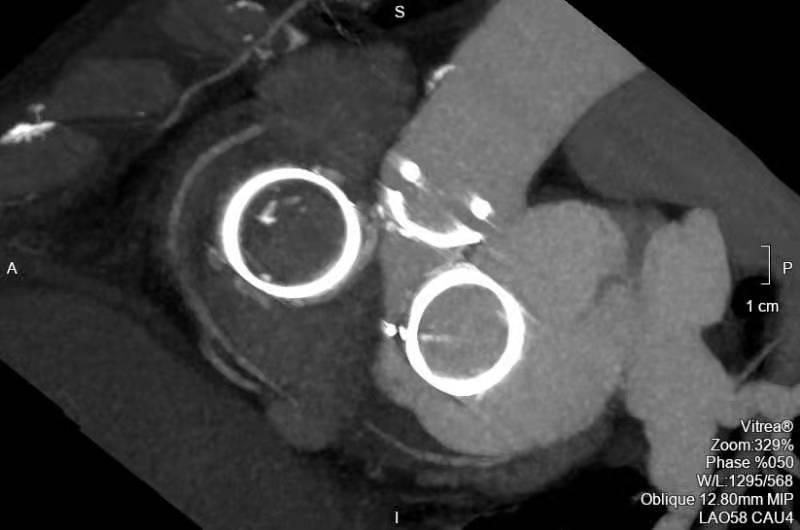

CT重建影像强强联合,绝处逢生

3月5日,沪豫联合手术团队为患者实施了主动脉瓣、二尖瓣、三尖瓣联合“瓣中瓣”置换手术。由于患者病变复杂,团队采用了三种不同路径植入三个瓣位。首先经左侧股动静脉分别穿刺置入主动脉根部猪尾导管和临时起搏电极,再穿刺右侧股动脉,顺利完成23毫米主动脉瓣“瓣中瓣”植入。然后经心尖途径,顺利完成27毫米二尖瓣“瓣中瓣”植入。最后穿刺右侧股静脉,成功完成29毫米三尖瓣“瓣中瓣”植入。经主动脉、左室、右室分别造影以及TEE检查,3枚瓣中瓣植入位置完美,瓣膜开合正常,压差均在理想范围内,无瓣中及瓣周返流,双侧冠脉显影理想。术中血流动力学平稳,无传导阻滞和流出道梗阻等并发症发生,几乎无出血。手术取得了圆满成功!